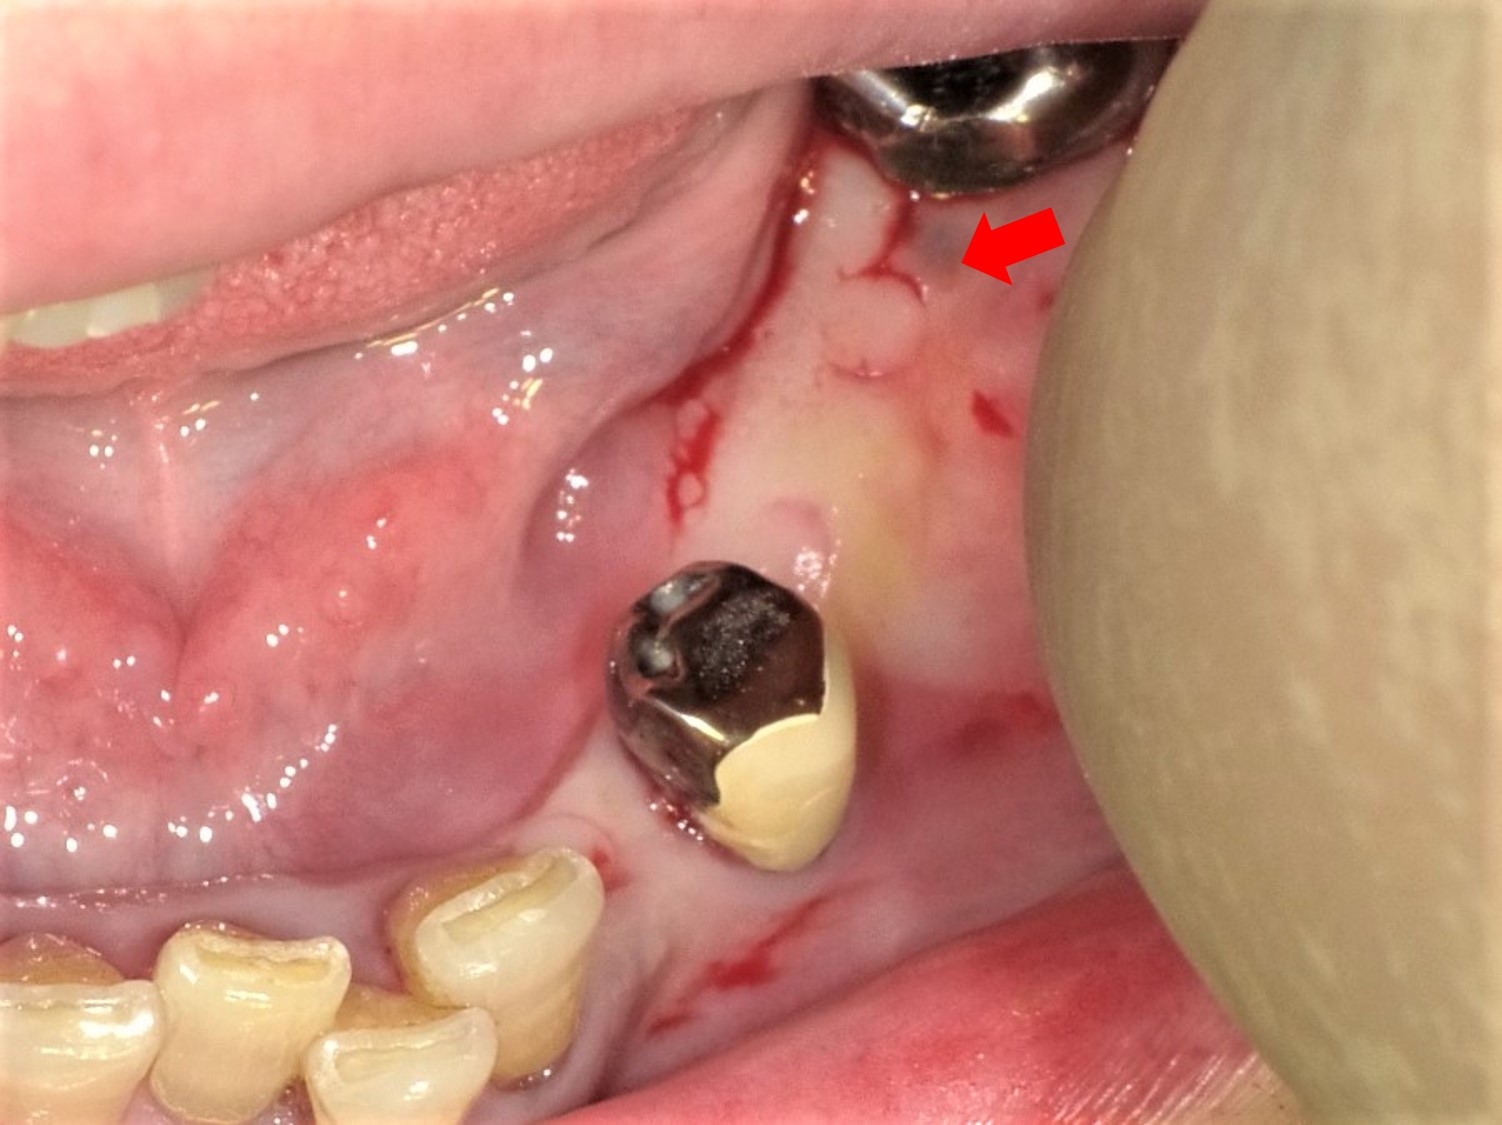

スキャンするために裁断したものです。※背表紙を切断していますので、普通の本のようには読めません。全てのページが一枚一枚バラバラになっております。ご注意下さい。裁断しているため、「全体的に状態が悪い」にしてあります。書き込みは見落としがあるかもしれませんが読む分には問題なく綺麗な状態です。袋に梱包しております。まとめ売りで送料分お値引きさせて頂きますので、ご希望の場合はコメントをお願いいたします。多数(冊)ご購入の場合は大幅にお値引きさせて頂きます。お値引き後の価格はこちらから提示させて頂きます。※仕事の都合上返信のお時間があまり取れません。単品でのお値引きを希望する場合のコメントは受け付けておりません。また、過剰なお値引きはご遠慮願います。その場合のコメントは削除またはスルーさせて頂きますのでご了承下さい。即決購入可能です。返品はご容赦ください。多数歯欠損・無歯顎症例のインプラント治療 林 揚春 他著 武田 孝之 他著ブランド:ー著作者:林 揚春 他著 武田 孝之 他著出版者名:ゼニス出版発売者名:鍬谷書店出版年月:201006価格:22,000円(税抜)多数歯欠損・無歯顎症例のインプラント治療に関する専門書。- タイトル: MAXILLA-ORIENTED IMPLANTOLOGY- 著者: 林 博幸, 井村 幸之, 鈴木 隆志- ISBN: 978-4-901510-19-8- 内容: 多数歯欠損・無歯顎症例のインプラント治療ご覧いただきありがとうございます。